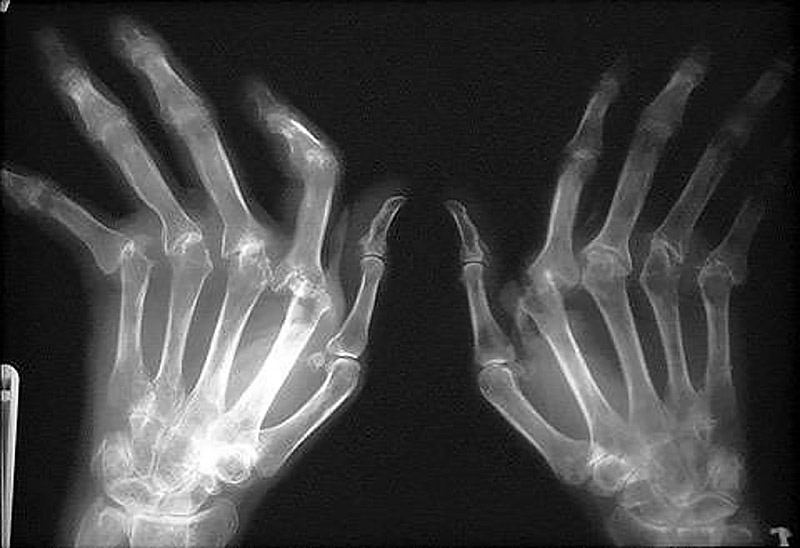

Основной способ диагностики полиартрита — контрастная рентгенография. Проведение данного

- обследования позволяет установить следующие изменения:

- анкилозивные нарушения, преобладающие над эрозивными;

- слабо выраженная деформация плюсне-фаланговых суставов;

- легкие проявления остеопороза;

- значительное поражение суставов запястья;

- легкие изменения в мелких суставах кисти.

Обследованием и лечением больных с подозрением на серонегативный или серопозитивный ревматический полиартрит занимается врач-ревматолог. Диагноз выставляют при наличии длительного поражения трех и более суставов, что подтверждается результатами рентгенографического обследования.